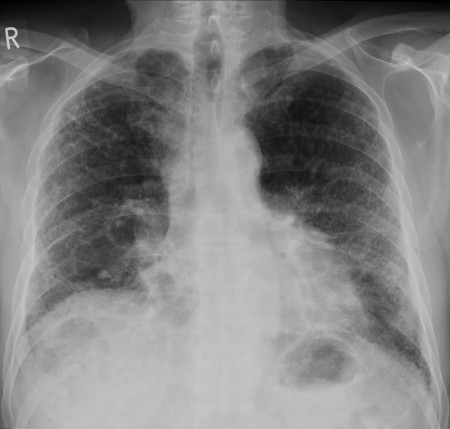

وانگ و همکاران گفتند این سیتیاسکن از یک زن ۳۵ ساله مبتلا به ویروس کروناست که نشان داده است برخی از آسیبهای ریه حتی پس از بهبودی باقی میماند.

همانطوری که مشاهده میکنید، هنگامی که این بیمار در بیمارستان بستری شد یک اسکن نشان داد که بافت یا مایعات باعث انسداد رگهای خونی در هر دو ریه میشود.

برخی از بافتها تا روز پانزدهم، چند روز قبل از اینکه بیمار از بیمارستان ترخیص شود، بهبود یافتند، اما برخی از این بافتها ممکن است در ریه ماندگار شوند؛ بنابراین با توجه به گسترش وسیع این بیماری همهگیر، مشکلات ریوی ناشی از کووید ۱۹ ممکن است سلامتی هزاران نفر را در سالهای بعد تهدید کند.